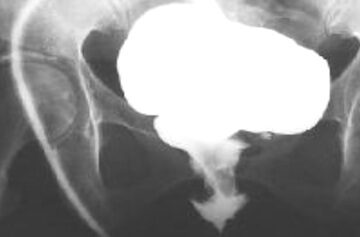

Цистография

При наличии пузырно-влагалищного свища определяется «вытекание» контрастного препарата через свищ за пределы мочевого пузыря при его ретроградном заполнении.

Рисунок 6.

Рисунок 6. цистограмма – экстравазация контрастного раствора из мочевого пузыря во влагалище через пузырно-влагалищный свищ.